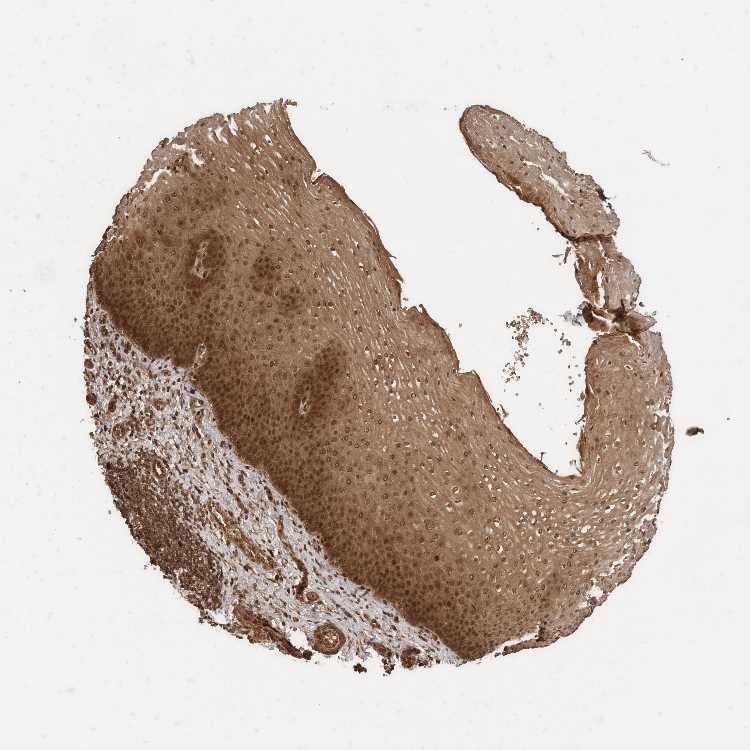

ESOPHAGUS - Antibody stainingi

Antibody staining in the annotated cell types in the current human tissue is reported as not detected, low, medium, or high, based on conventional immunohistochemistry profiling in selected tissues. This score is based on the combination of the staining intensity and fraction of stained cells.

Each image is clickable and will lead to virtual microscopy that enables deeper exploration of all samples and also displays staining intensity scores, fraction scores and subcellular localization as well as patient and tissue information for each sample.

Antibody HPA023319Antibody HPA023320Antibody HPA023321Antibody HPA023325

Squamous epithelial cells HighMediumHighHigh